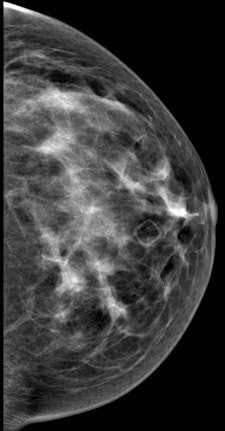

Breast cancer findings include masses, calcifications, developing asymmetry, and skin thickening, which is often imperceptible, Shaheen said. For whatever reason the patient is called back -- a finding on mammography, a clinical finding, or a patient discovering a symptom -- the diagnostic path generally begins with multimodality imaging, followed by image-guided biopsy. Then comes the critical rad-path correlation and, ultimately, assessment of cancer pathology and hormonal status before deciding on treatment, which greatly depends on the individual case.

According to the 2013 American College of Radiology (ACR) guidelines, breast MRI should be performed for screening high-risk patients, as well as those with a new breast malignancy, following a 2007 report in the New England Journal of Medicine on MRI's ability to find cancer in the contralateral breast. It should also be used to screen patients with breast augmentation, which presents difficulties such as mammographically occult regions, or cancer tracking the contour of the implant, Shaheen said.

For confirmed cancers, MRI can be used to assess the extent of disease such as ductal carcinoma in situ, for additional evaluation of imaging or clinical findings, and for problem-solving.